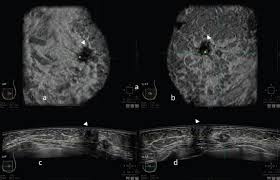

The rate of breast cancers discovered as dcis is thought to be increasing, but this is partially a testament to the effectiveness of mammographic breast cancer screening programs.ductal carcinoma in situ represents up to 30% of all new cases of breast cancer discovered by breast cancer screening. On ultrasound, a breast cancer tumor is often seen as hypoechoic, has irregular borders, and may appear spiculated. A specialist looks at the ultrasound pictures. Depending on your symptoms, your doctor makes a diagnosis based on a combination of tests and procedures. Below are images of dcis on breast ultrasound. If there are calcifications within the nodular dcis, one may be able to see these on ultrasound as white flecks. Is tender, aches or feels painful. X trustworthy source mayo clinic educational website from one of the world's leading hospitals go to source research suggests that men are more likely to ignore breast lumps than women, but early. During a breast exam, your doctor looks for visual changes and uses their fingers to feel. What does breast cancer look like on a mammogram? The symptoms of ibc include a breast that: (1) gary ulaner, md, phd, facnm. Notice that there is some fibroglandular tissue on the right, while on the left there is only subcutaneous fat.

However, a dark spot on your ultrasound doesn't mean that you. Characteristics of malignant breast cancer on ultrasound are speculation, deeper (taller) than wide, microlobulations, thick hyperechoic halo, angular margins, markedly hypoechoic nodule, posterior acoustic shadowing, branching pattern, punctate calcifications, duct extension and heterogeneous echotexture. Signs of inflammatory breast cancer. Mammography is the least sensitive imaging. Breast ultrasound breast ultrasound uses sound waves to make a computer picture of the inside of the breast.

Early warning signs of inflammatory breast cancer along with images of inflammatory breast cancer are mentioned below. There is a slight increase in the density in the right breast compared with the left. Rate of dcis discovery is increasing, due to screening mammograms. Cysts, tumors, and growths will appear as dark areas on the scan. Any area that does not look like normal tissue is a possible cause for concern. Finding breast lumps and seeing change in the size and shape. Ultrasound is one of the tools used in breast imaging, but it does not replace annual mammography. When is breast ultrasound used? Ibc is a rapidly progressive, aggressive form of breast cancer associated with a low overall survival rate. Some early breast cancers only show up as calcifications on mammography. Has skin that looks dimpled or ridged like an orange. Generally speaking, the denser the tissue, the whiter it appears. Instead, breast skin can become thick, red, and look pitted, like an orange peel.